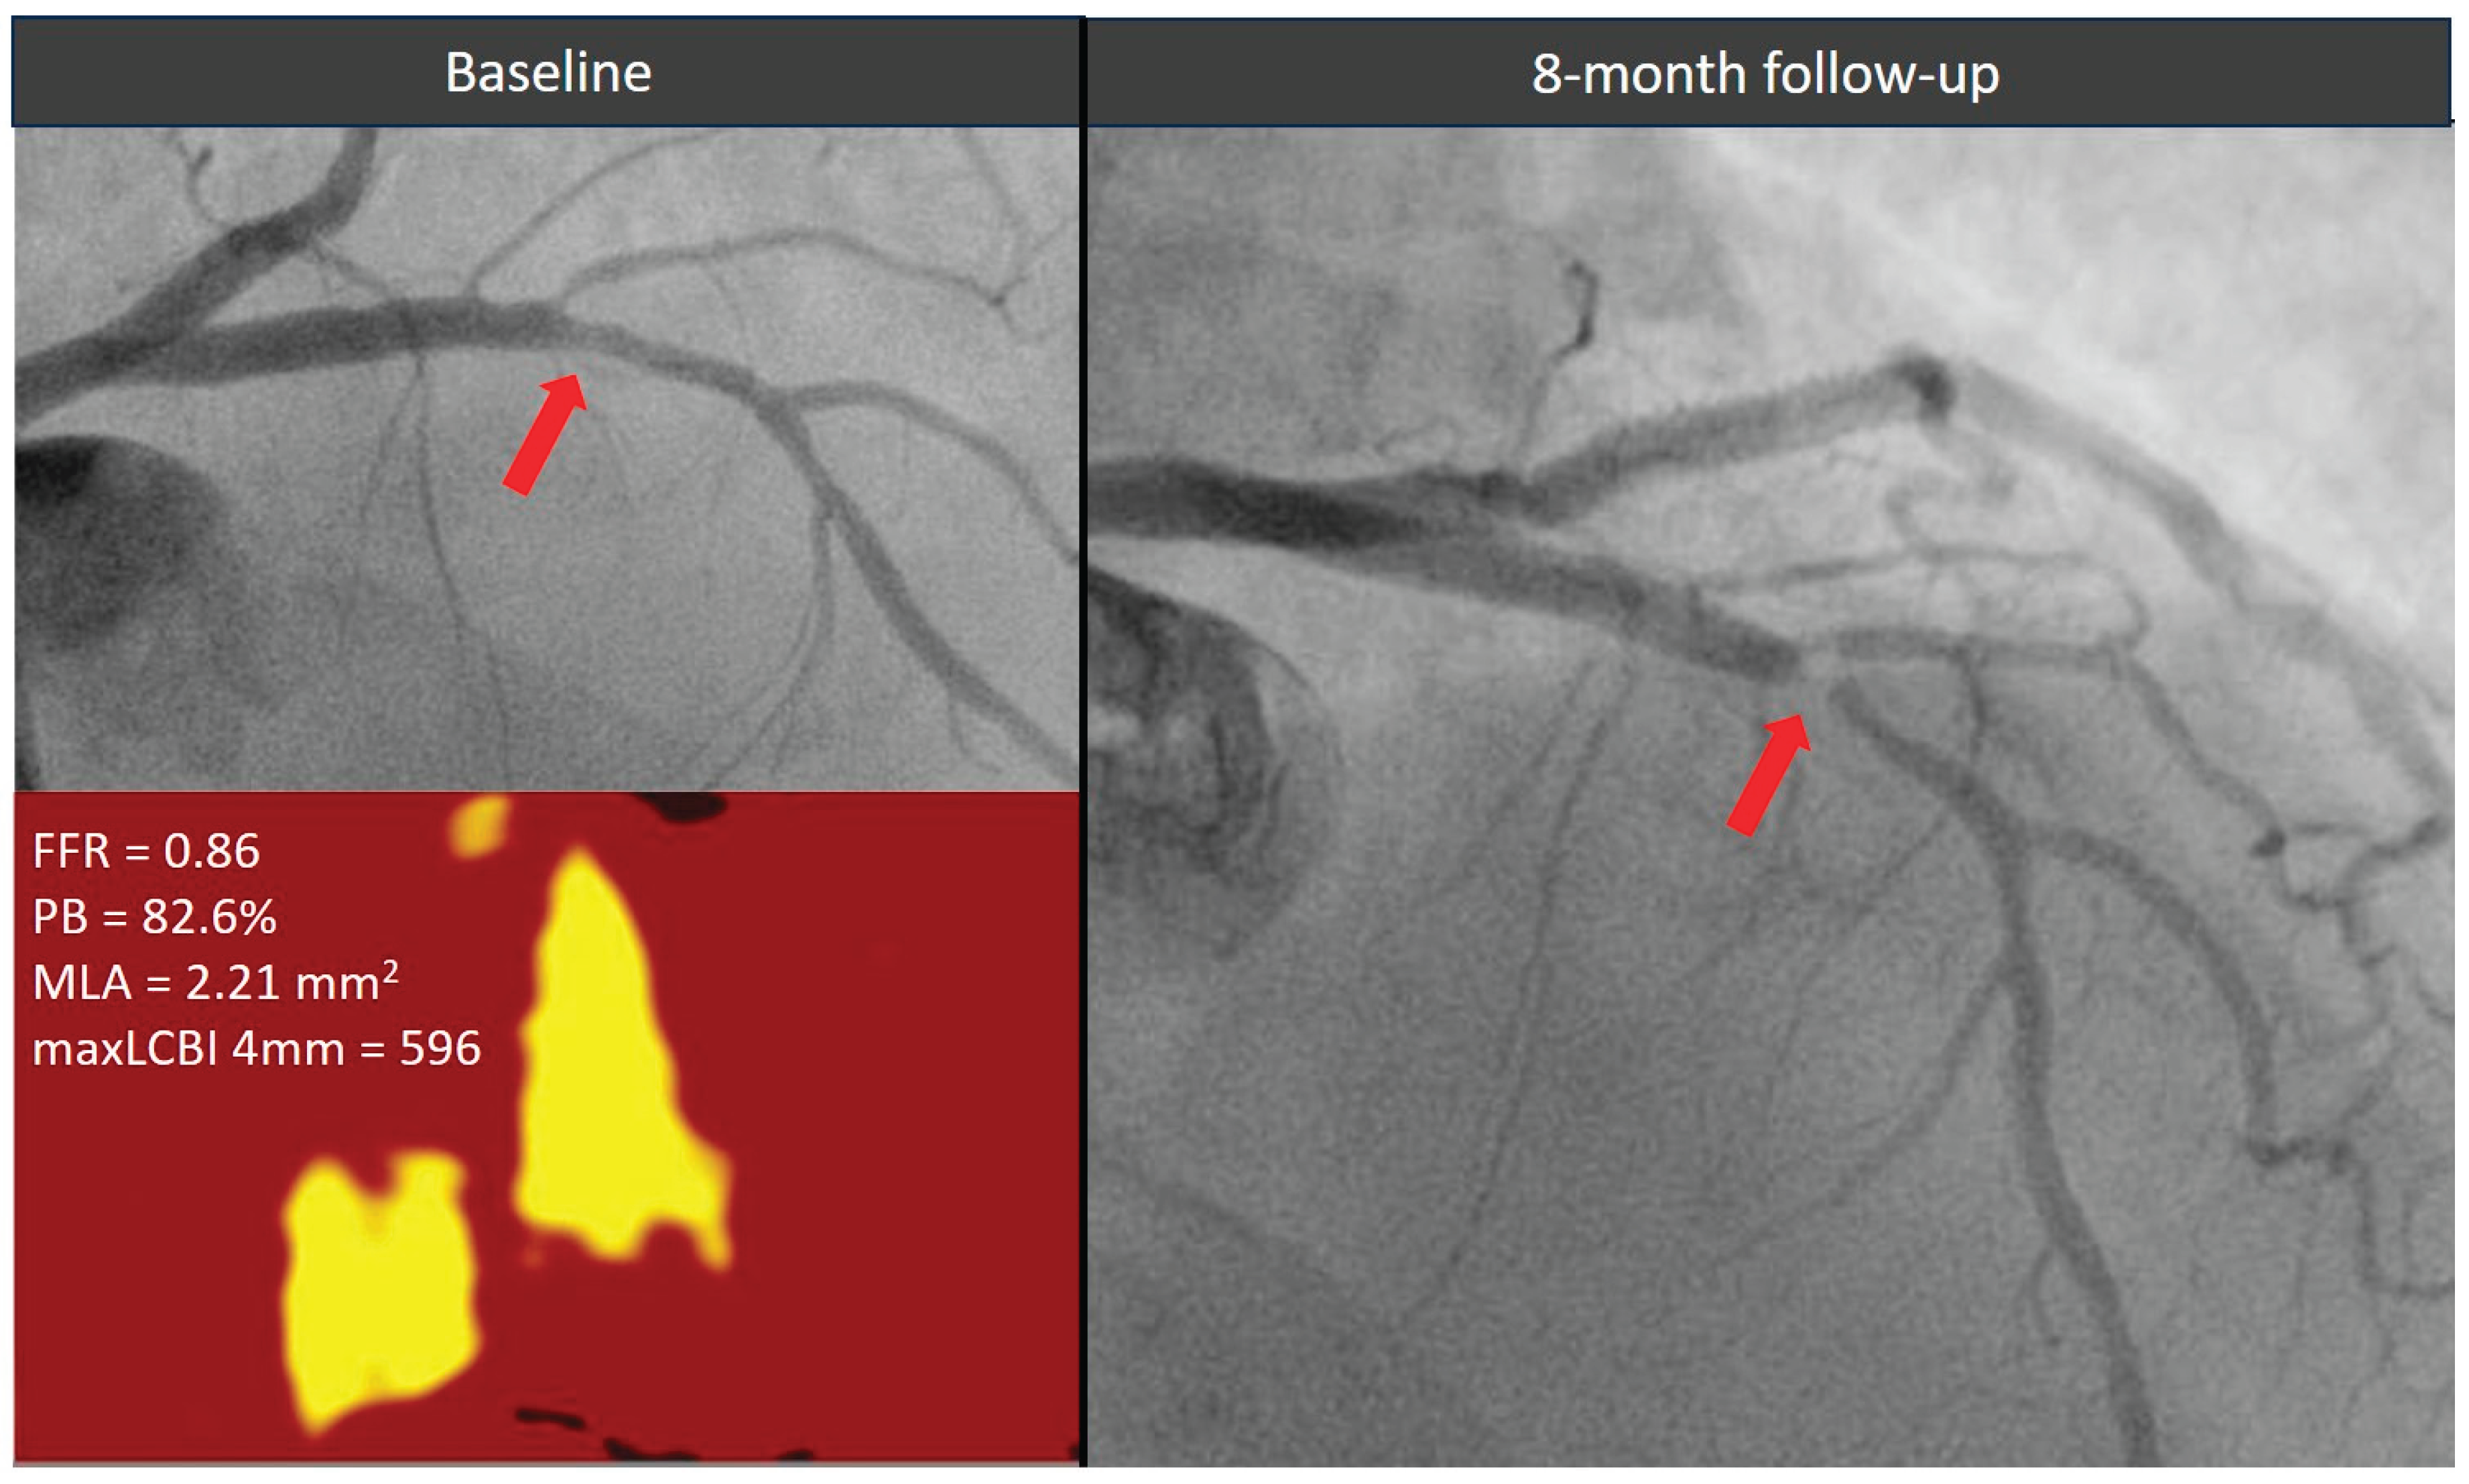

Figure 3. Evolution of a functionally non-significant proximal left descending artery lesion (red arrow) exhibiting all three high-risk morphological features. The plaque showed a significant stenosis progression causing an acute coronary syndrome within 1 year from the index angiogram. FFR = fractional flow reserve, MaxLCBI4mm = maximum lipid core burden index within any 4 mm segment, MLA = minimal lumen area, PB = plaque burden.